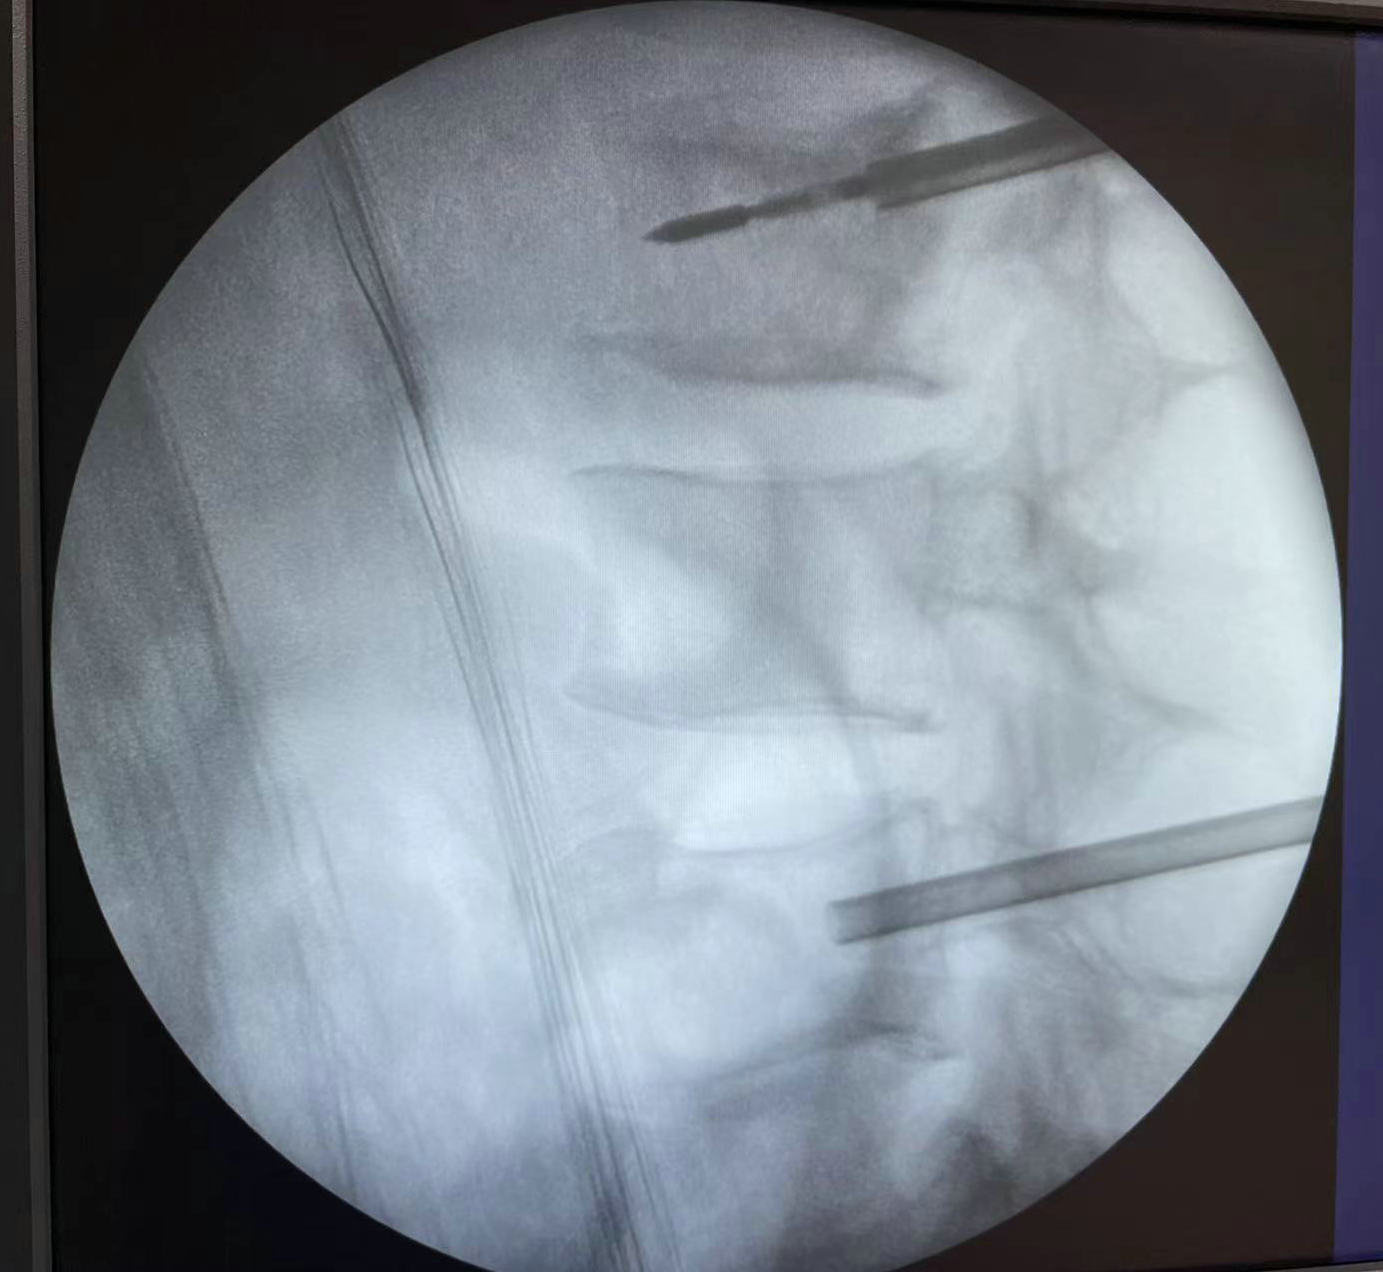

术中微波消融情况